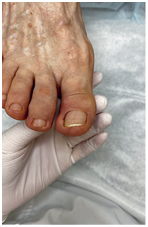

Иллюстрация к книге — Подология понятно. Важен каждый шаг. Справочник по проблемам подологии для клиентов и мастеров эстетики [i_270.jpg]

Результат работы за 5 месяцев: подолог использовал крючковые коррекционные системы, а хирург сделал пластику внутреннего бокового валика (из-за хронических воспалений боковой валик стал гипертрофированным и давил на ноготь, от чего клиент испытывал постоянный дискомфорт)